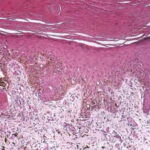

onset of a nodule, with development of ulceration . However, some acral melanomas may be deeply invasive while remaining quite flat because the thick stratum corneum seems to act as a barrier to exophytic growth. Histopathology. The lesions are termed lentiginous because the majority of the lesional cells are single and located near the dermal-epidermal junction, especially at the periphery of the lesion . However, usually some tumor cells can be found in the upper layers of the epidermis, especially near areas of invasion in the center of the lesions. The histologic picture differs from that of lentigo maligna because of irregular acanthosis, the lack of elastosis in the dermis, and the frequently dendritic character of the lesional cells . Early in situ or microinvasive lesions may show, especially at the periphery, a deceptively subtle histologic picture consisting of an increase in basal melanocytes and hyperpigmentation with only focal atypia of the melanocytes. However, in the center of the lesions, there is usually readily evident uniform, severe cytologic atypia. There may be a lichenoid lymphocytic infiltrate that may largely obscure the dermal-epidermal junction, and in some cases this may be so dense as to simulate an inflammatory process. In most of the lesions, both spindle shaped and rounded, pagetoid tumor cells are seen, and, in many cases, pigmented dendritic cells are prominent. Pigmentation is often pronounced, resulting in the presence of melanophages in the upper dermis and of large aggregates of melanin in the broad stratum comeum. As in lentigo maligna, when tumorigenic vertical growth phase is present, it is often of the spindle cell type and not uncommonly desmoplastic and/or neurotropic. In |